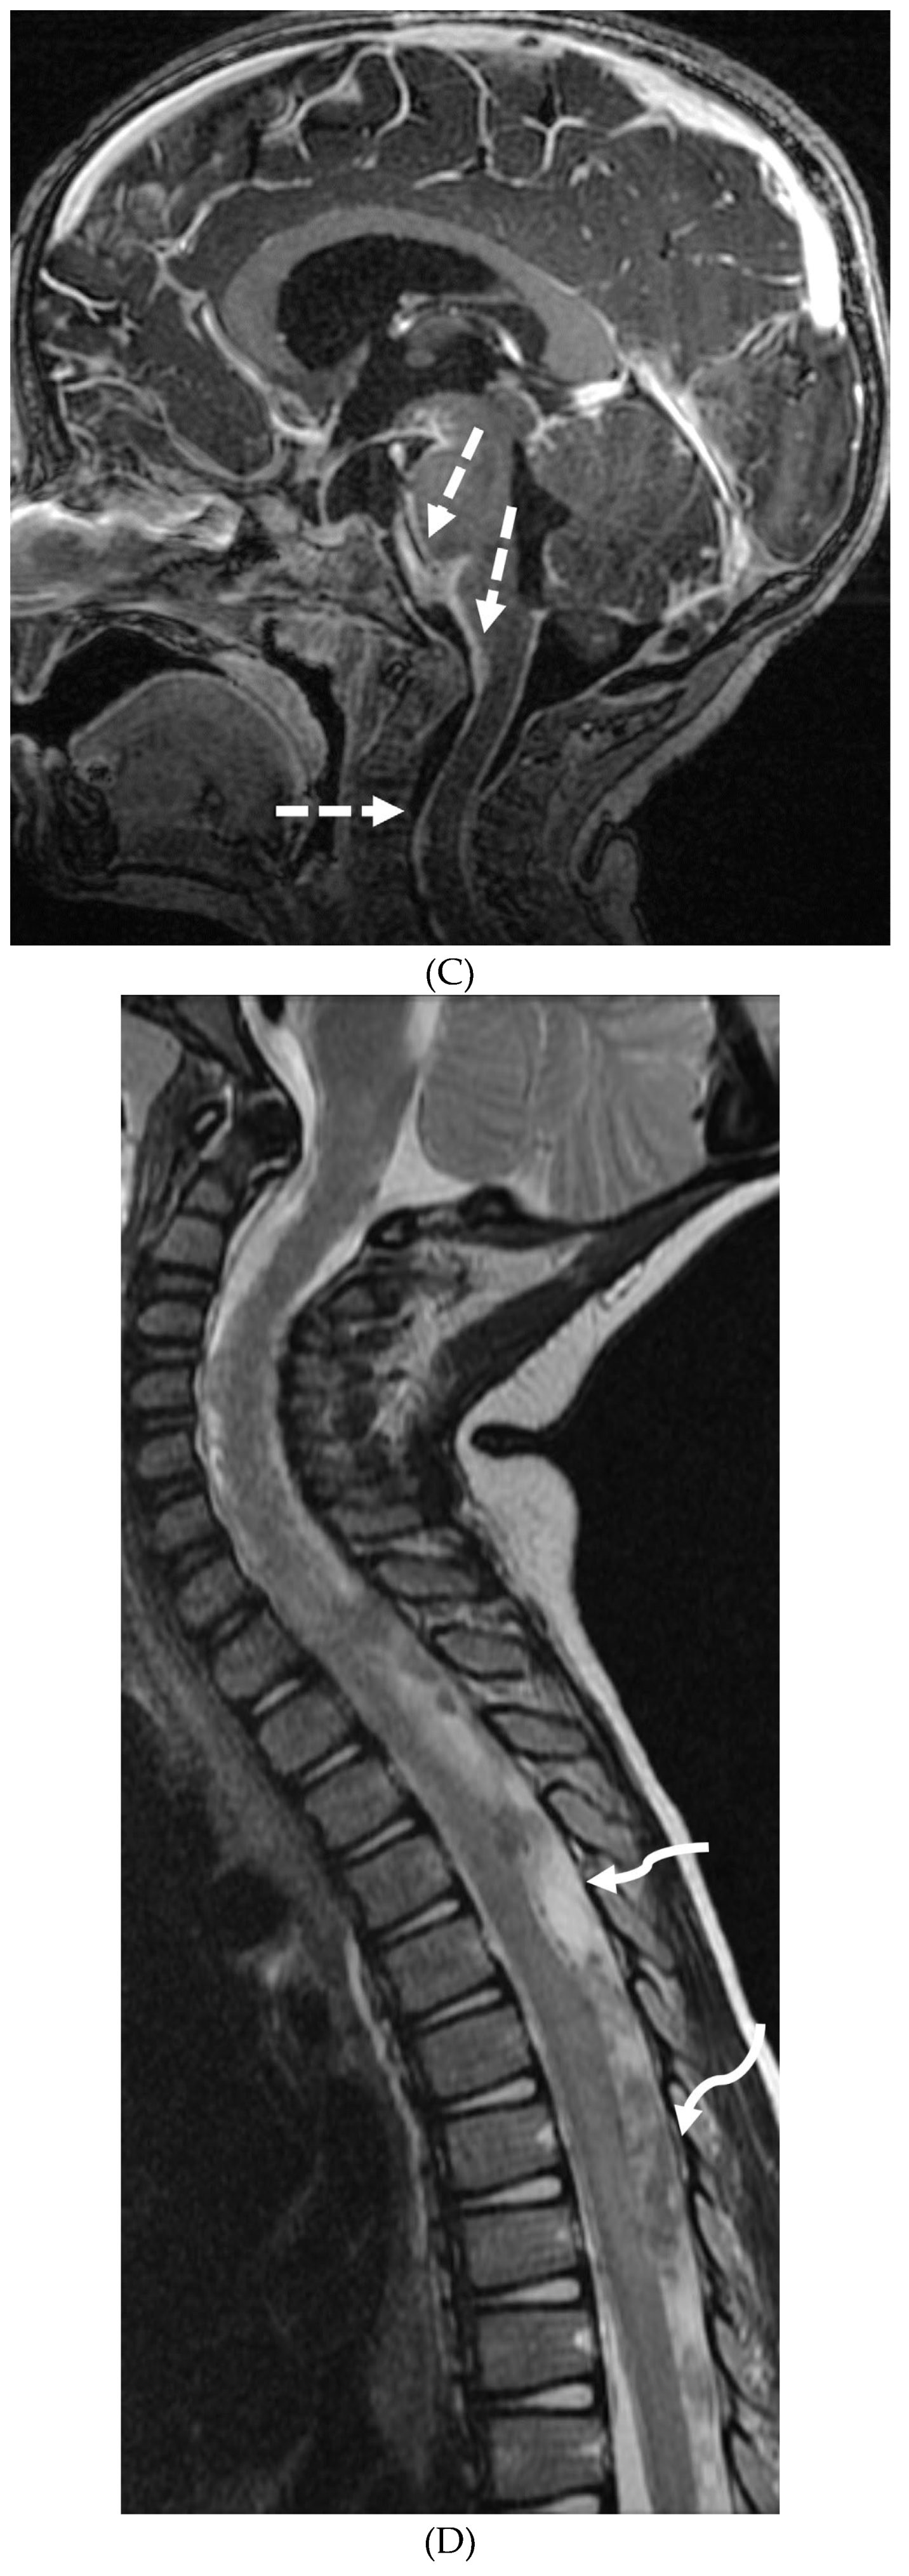

INTRACRANIAL HYPOTENSION (IH)

- Peterson EE, Riley BL, Windsor RB. Pediatric Intracranial Hypotension and Post-Dural Puncture Headache. Semin Pediatr Neurol. 2021 Dec;40:100927. Epub 2021 Sep 3. PMID: 34749914. [CrossRef]

- Schievink WI, Maya MM, Louy C, Moser FG, Sloninsky L. Spontaneous intracranial hypotension in childhood and adolescence. J Pediatr. 2013 Aug;163(2):504-10. Epub 2013 Feb 28. PMID: 23453548. [CrossRef]

- Shah LM, McLean LA, Heilbrun ME, Salzman KL. Intracranial hypotension: improved MRI detection with diagnostic intracranial angles. AJR Am J Roentgenol. 2013 Feb;200(2):400-7. PMID: 23345364. [CrossRef]

- Yuh EL, Dillon WP. Intracranial hypotension and intracranial hypertension. Neuroimaging Clin N Am. 2010 Nov;20(4):597-617. PMID: 20974378. [CrossRef]

- Medina JH, Abrams K, Falcone S, Bhatia RG. Spinal imaging findings in spontaneous intracranial hypotension. AJR Am J Roentgenol. 2010 Aug;195(2):459-64. PMID: 20651205. [CrossRef]